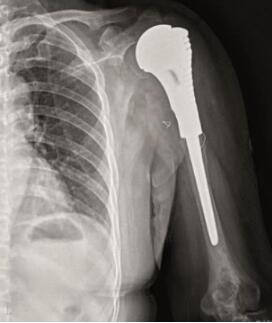

患者内固定物断裂,肱骨头塌陷,肱骨近端形态发生变化,需重建肱骨近端和肩关节的解剖形态,现有肩关节和反肩关节虽然能够解决关节之间匹配的问题,但对于肱骨近端有大块畸形的骨缺损无能为力。在此基础上,取得患者的知情同意后,对该患者的肩关节进行个体化的设计和制造(图1)。

图1 患者术前X线及三维重建图像A.X线;B.CT三维重建图像。